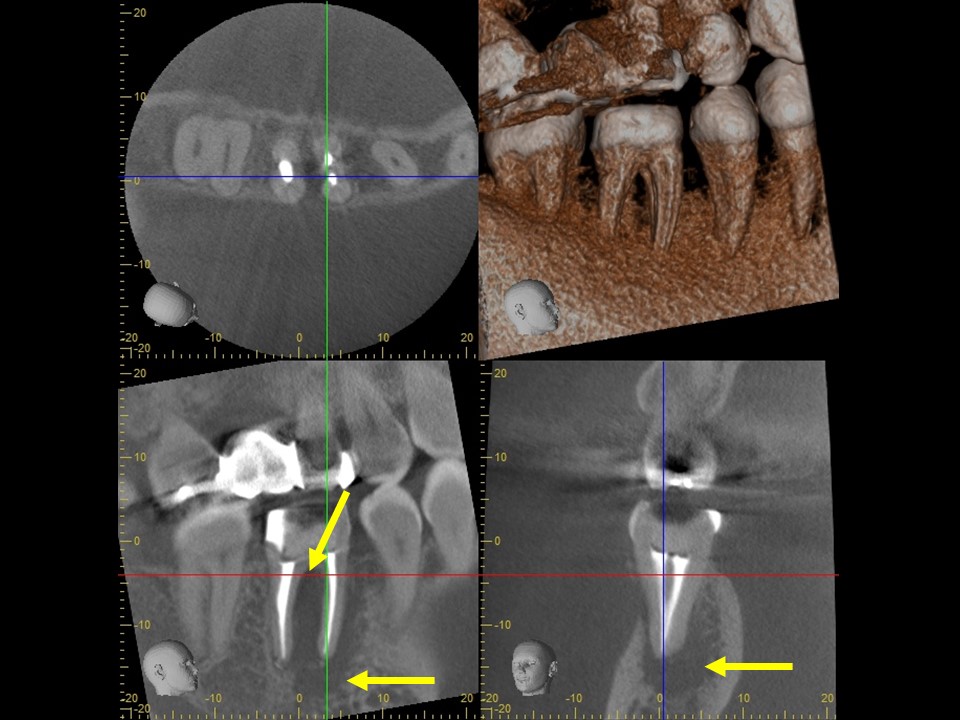

初診時レントゲンおよびCT画像です。すでに根管治療はされているが、根尖まで薬が入っておらず、根尖病変と思われる黒い透過像を認めます(矢印)